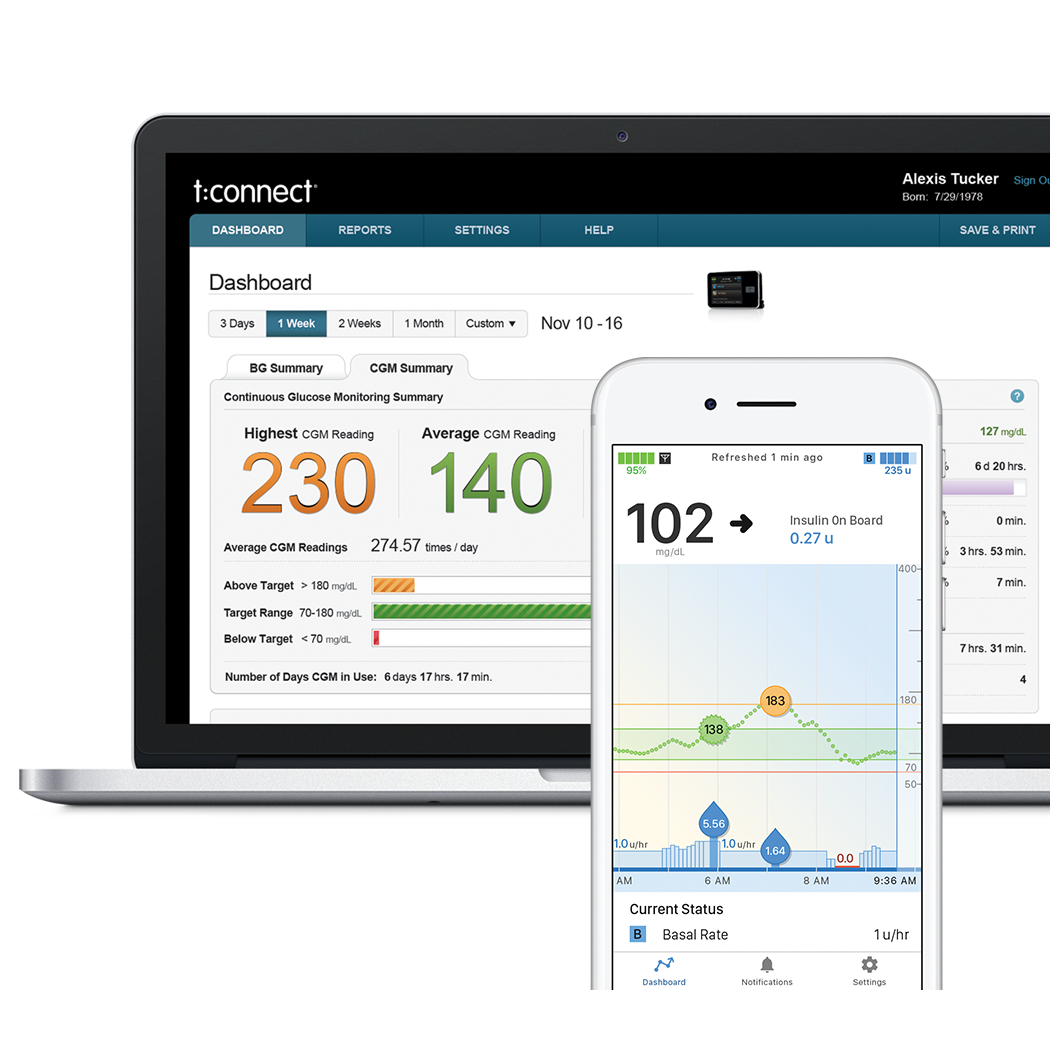

La aplicación móvil t: connect® sirve como una pantalla secundaria discreta para su bomba de insulina t: slim X2, para que pueda mantenerse informado sobre el manejo de su diabetes desde la comodidad de su teléfono. Vea los datos de su bomba, incluidos los eventos de insulina basal y de bolo, la insulina a bordo, los carbohidratos, la configuración y el estado de la bomba y el sensor.

Con solo unos pocos clics en su Bomba de Insulina t:slim X2, usted puede ver su administración de insulina y su historial de glucosa. También puede cargar los datos de la Bomba de Insulina t:slim X2 de forma inalámbrica a través de la aplicación móvil t:connect® eliminando así la necesidad de conectar la bomba en el consultorio del médico.